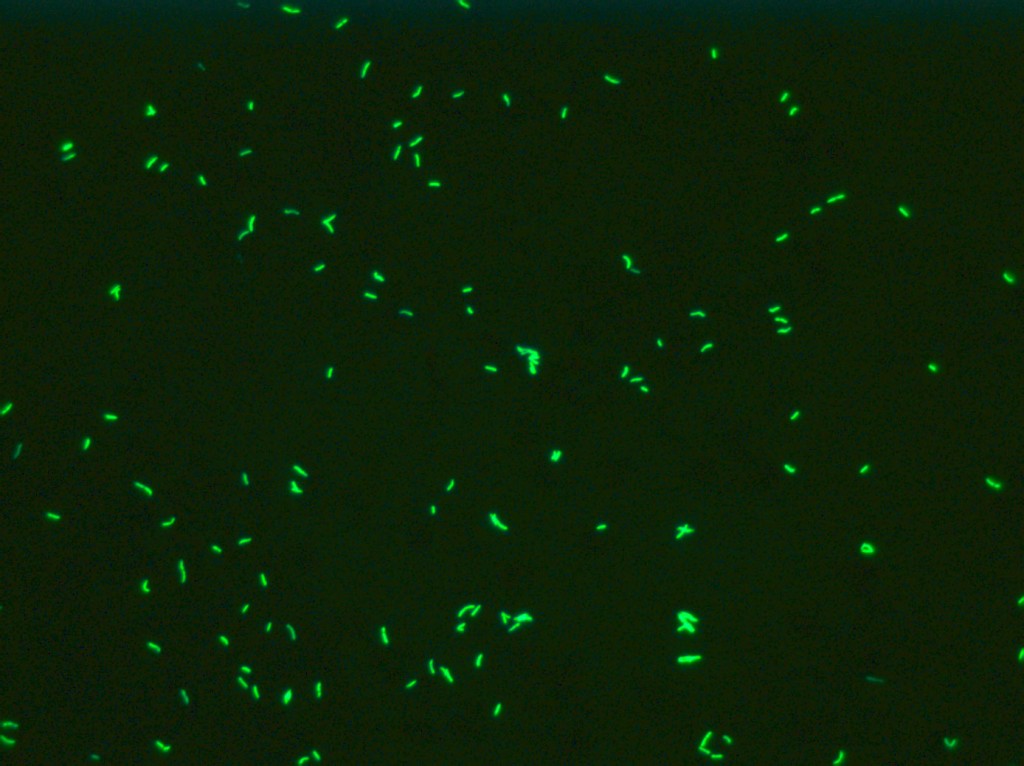

Cette carte de concepts créée avec IHMC CmapTools traite de: Diagnostic, Tuberculose urinaire on peut observer Cystite Hématurie microscopique Leucocyturie aseptique, m.Tuberculosis utilisation de glycérol (LOEWENSTEIN-JENSEN), Volailles On peut observer Aspergillose, tuberculose miliaire on observe lésions anciennes caséeuses et tubercules gris, test à l'interféron gamma est rapide, Primo-infection stabilisée on observe tubercules caséeux arrondis, jaunâtres de quelques mm Noeuds lymphatiques caséeux, Intradermotuberculinisation chez Homme, Nécropsique chez Bovins, Bovins si Généralisation précoce lente, Tuberculose extra-pulmonaire comme Tuberculose génitale, Aspergillose avec pseudo-tubercules jaunes caséeux lésions exclusivement pulmonaires, Prélevements de liquide pleural, Nécropsique si suspicion de TB prélevement des noeuds lymphatiques et des organes, tuberculose pulmonaire on peut observer signes cutanés, Intradermotuberculinisation grâce à des tuberculines, 3 mois si négatif, signes fonctionnels et généraux comme fièvre, Bovins si Primo-infection stabilisée, Hématoxyline-Eosine montrent Cellules de Langerhans, Tuberculose extra-pulmonaire comme Tuberculose cutanée